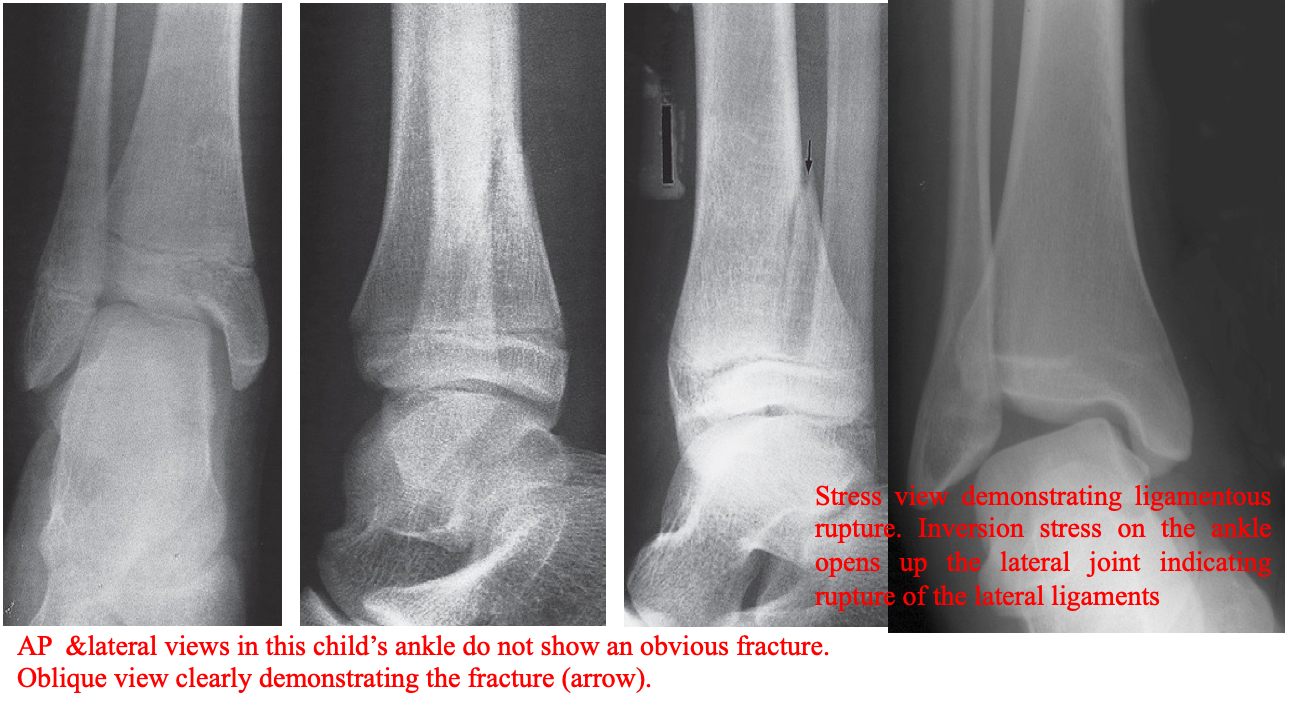

Injuries may sometimes be invisible even with two views taken at right angles to each other.

Further plain film views

- Different projections, e.g. oblique views

- Stress films: A film taken with a joint under stress; Stress films are helpful in ankle injuries when forced inversion and eversion may show movement of the talus.